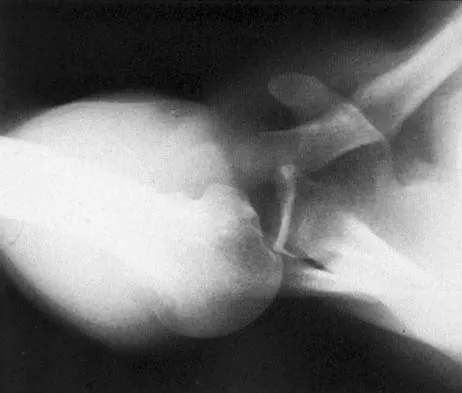

A 30-year-old man caught his dominant little finger on the straps of his windsurfing board 10 days ago. He reports swelling about the distal phalanx and has difficulty completely extending the distal interphalangeal joint. A radiograph is shown in Figure 47. What is the most appropriate treatment for this injury?

Detailed Explanation